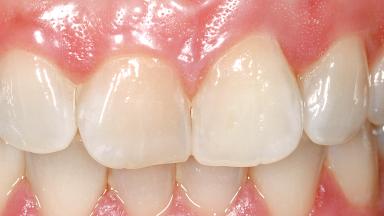

Immediate Flapless Placement of an Implant in a Maxillary Left Central Incisor Site

A 29-year-old female patient presented for treatment to replace the upper left central incisor tooth with an implant- supported restoration. The tooth had been intermittently symptomatic for the previous 12 months. The tooth had originally suffered trauma about 15 years previously. Several endodontic treatments had been performed, including an apicectomy procedure to retain the tooth. The patient was healthy and a non-smoker. She had reasonable expectations in regard to esthetic outcomes and the risk of marginal tissue recession following treatment. At medium smile, the gingival margins of the upper teeth were visible, with a display of 3 to 4 mm of the gingival margins. Gingival recession of tooth 21 and a discrepancy in the gingival levels between teeth 11 and 21 was observable during normal speech and smile.